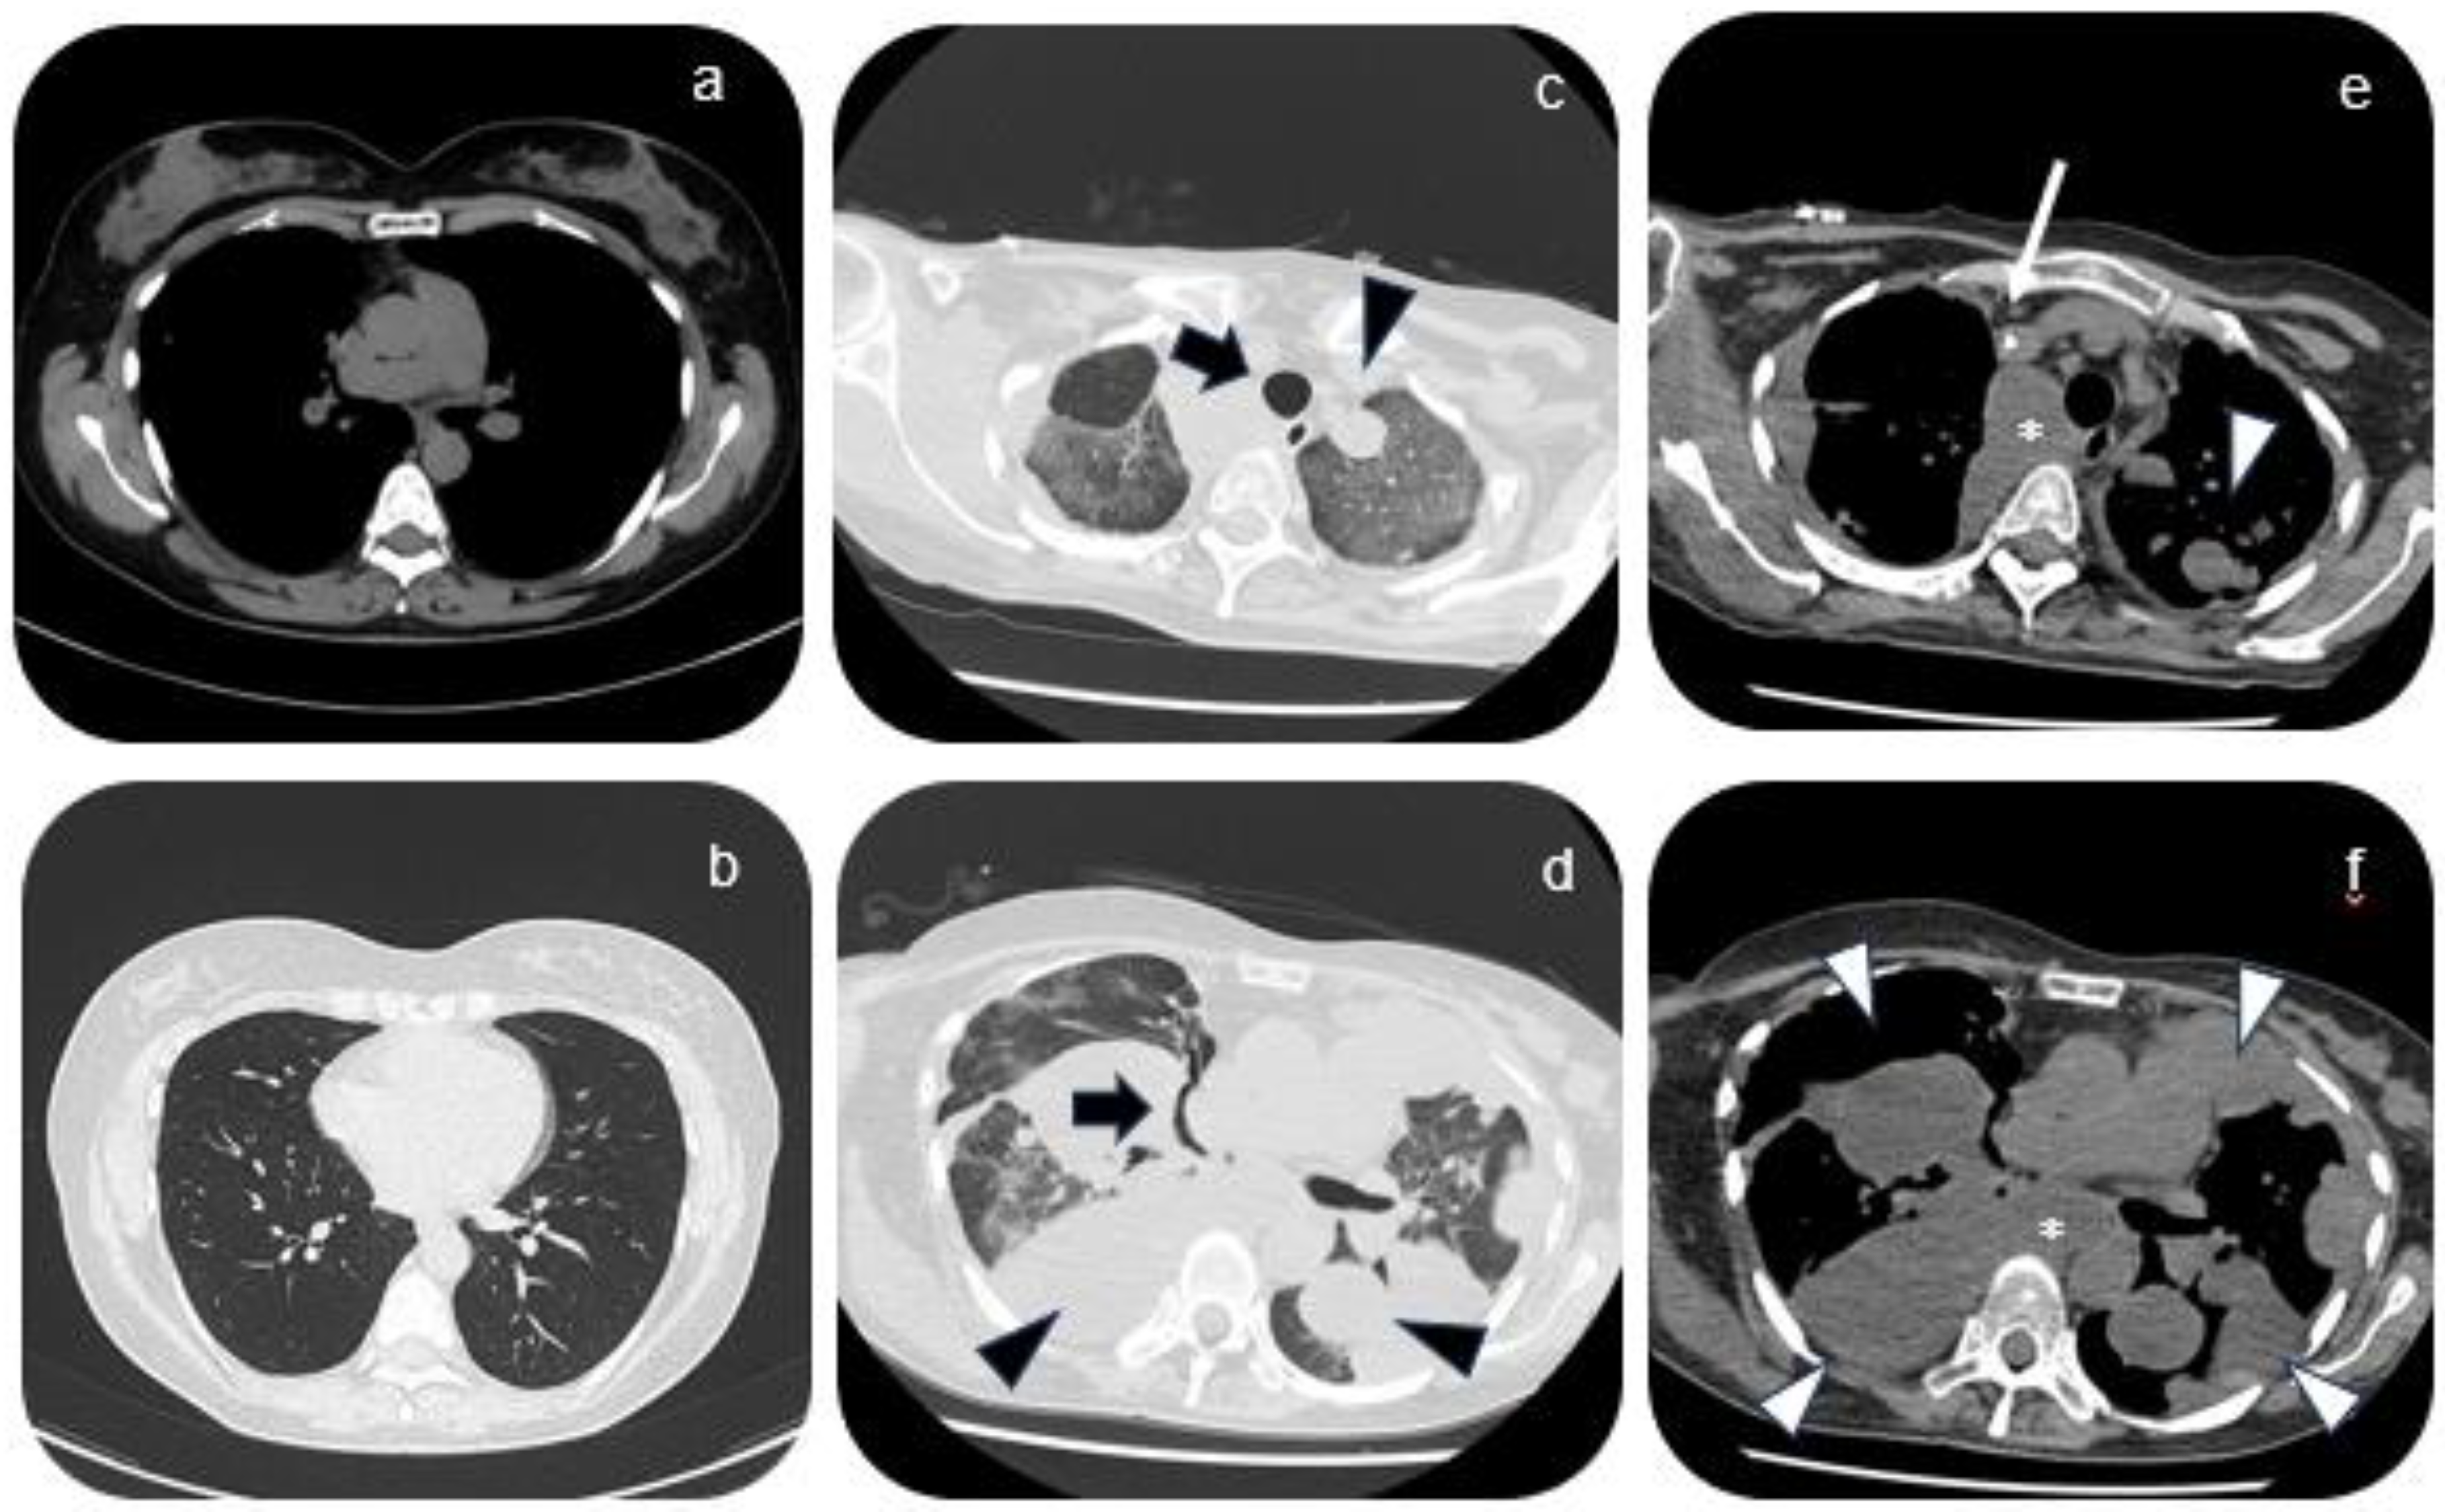

2. Case Presentation